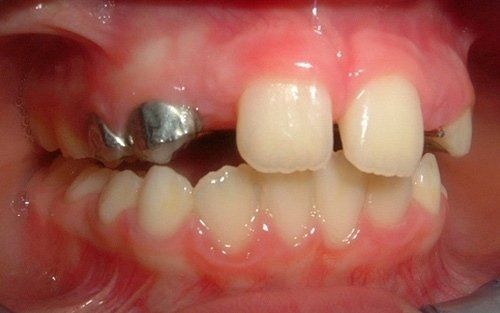

ORTODONZIA CLASSICA

Tramite brackets, ovvero attacchi (metallici, in resina o in ceramica) posizionati sui denti, viene realizzata una metodica fissa, con lo scopo di riallineare gli elementi dentari presenti in arcata raggiungendo la migliore occlusione possibile. L’opportunità di utilizzare una o l’altra tecnica, o una combinazione delle stesse dipende dalla diagnosi effettuata mediante le registrazioni iniziali.